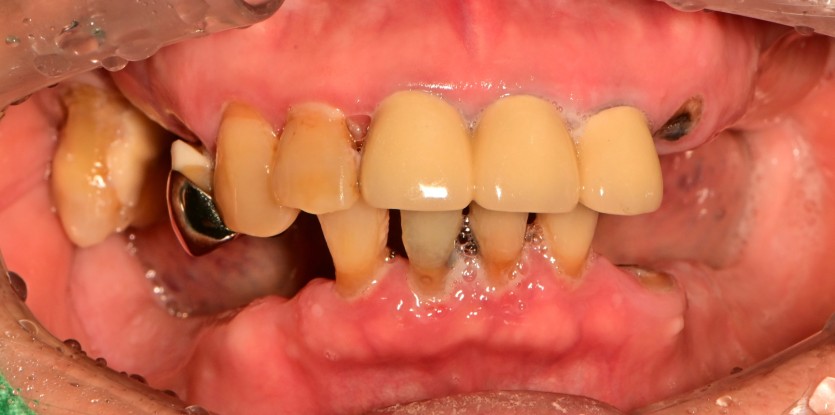

만 82세 하악 풀아치, 상악 임플란트(일부) 증례

하악 풀아치 증례입니다. (상악 구치부 임플란트 포함)

12개의 임플란트로 완성하였습니다.